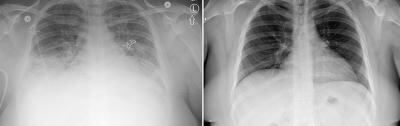

Los investigadores ya habían identificado este aceite como posible responsable de esta epidemia, pero sus sospechas fueron confirmadas por sus hallazgos en 29 pacientes cuyos fluidos pulmonares fueron analizados por los Centros de Control y Prevención de Enfermedades (CDC).

"Estos análisis proporcionan evidencia directa de que el acetato de vitamina E es la principal causa de daño pulmonar", dijo Anne Schuchat, subdirectora de los CDC. Acetato es el nombre químico de la molécula.

Schuchat señaló que "aún no se ha detectado ninguna otra toxina potencial en los análisis".